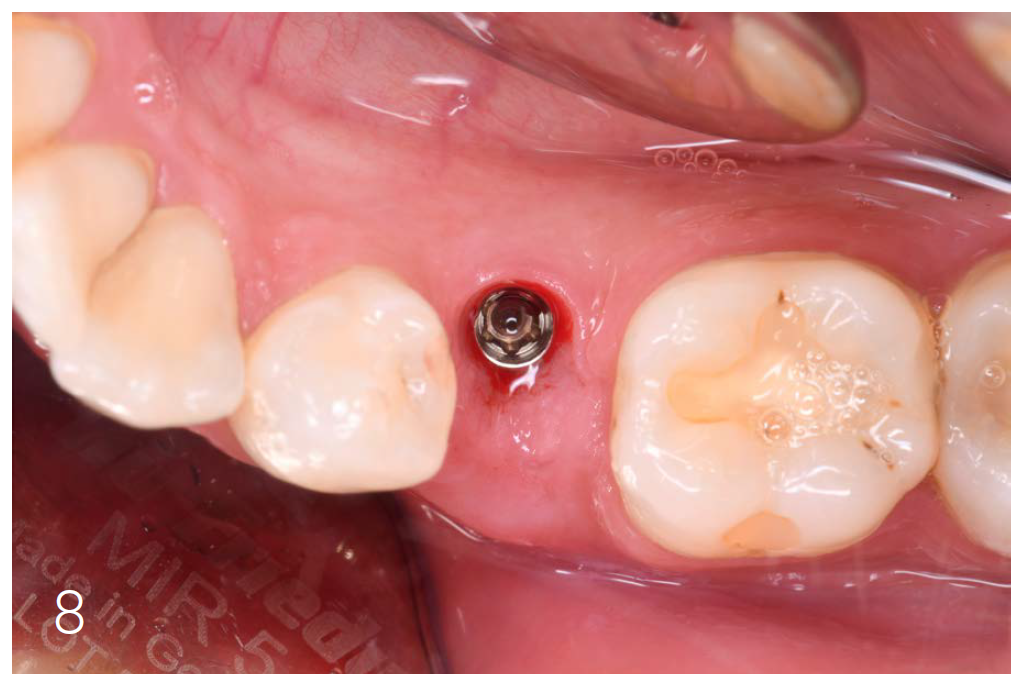

Figure 4: Condition after implantation

The Socket Shield Technique is not easy to perform. High-quality instruments are essential. Cuts must be fine and precise with minimal pressure. For this case, I used the H254LE 314 012 bone mill (Komet Dental) with a cross-cut design (right-right fluting), which runs smoothly and cuts efficiently. Its thin cut and controlled use in a red contra-angle handpiece make it ideal. I used it to section the tooth and shape the root remnant. Then, I refined the root with instruments 8831L, 831LEF, and ZR8801L (Komet Dental) - all of which allow fingertip control and effective cutting.

After osteotomy, I placed a 3.75 mm diameter implant, filled the gap between implant and root surface with allogenic bone substitute, inserted a provisional, and later restored with an aesthetic ceramic crown.

Figures 7 and 8: Clinical situation after 6 months